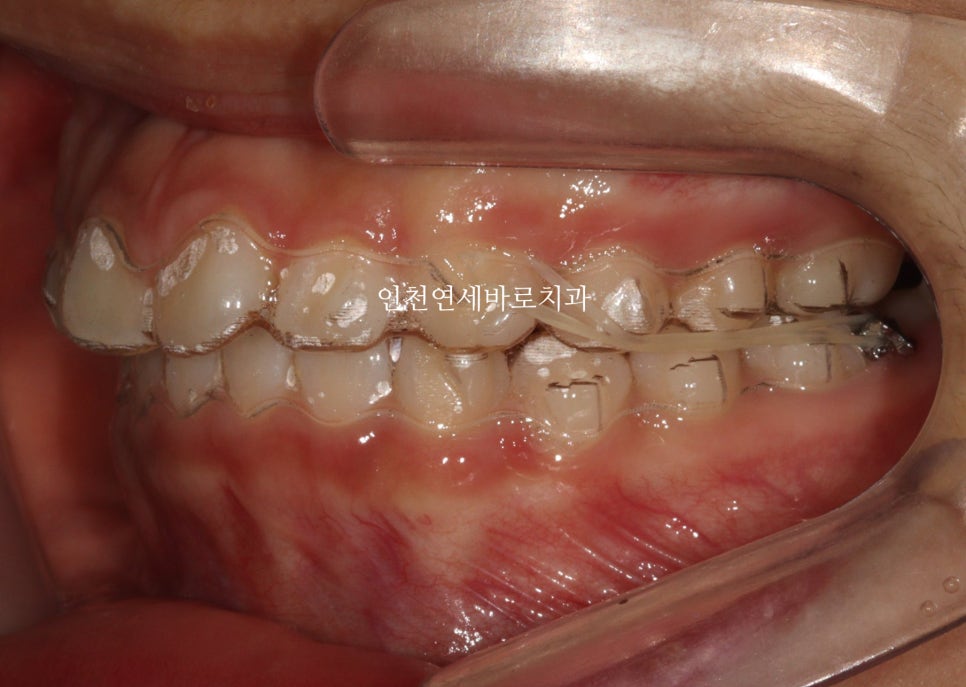

치료 전 상태 및 진단

인천연세바로치과에 온 환자아이입니다.

앞니가 튀어나와있고, 삐뚤삐뚤, 그리고

#과개교합

도 있는 아이었습니다.

| 초기 상태 | 앞니 돌출, 배열 불량, 과개교합 |